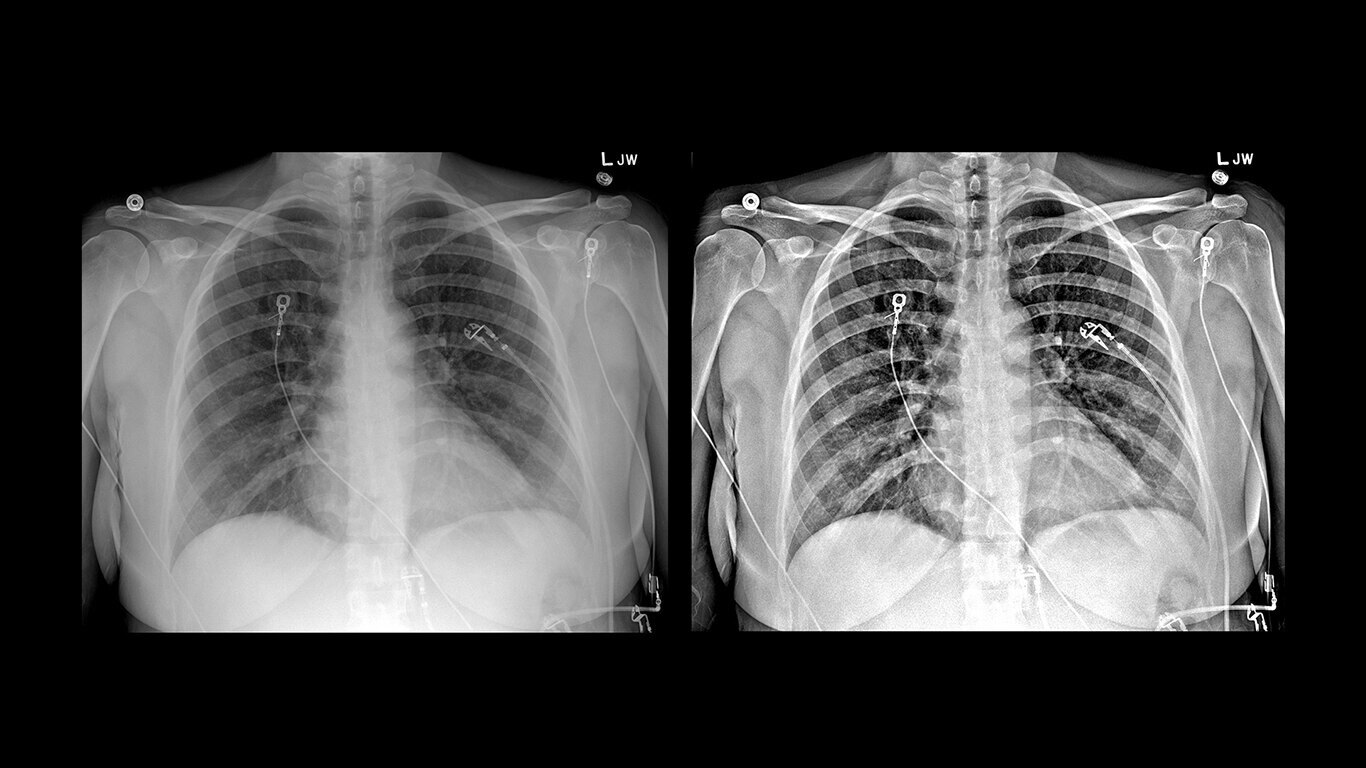

Uncompromised image quality

Capture high-resolution images with powerful, glassless detectors that weigh 40% less than previous generations3